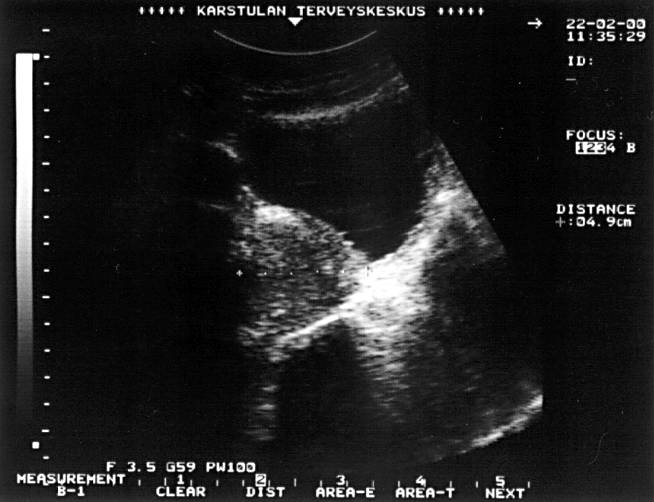

Prostatic hyperplasia (longitudinal ultrasonographic picture).Urinary retention in an elderly man was caused by a significantly enlarged prostate. The length of the prostate measures 4.9 cm and, measured from a transverse picture, the height is 4.8 cm and the width 5.5 cm. The estimated prostatic size is 0.6 × 4.8 × 5.5 × 4.9 = 77 ml and the weight is about the same in grams.

Picture: Ilkka Kunnamo